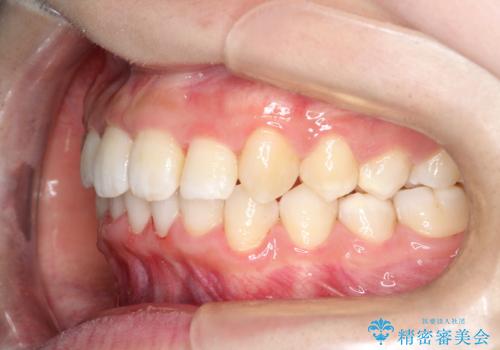

重度のガタガタのインビザラインによる非抜歯矯正

- 全体的なガタガタを気にされて来院されました。

抜歯矯正も考えられる状態でしたが、ご本人的になるべく歯を抜かない矯正を希望されました。

奥歯を後方に移動させるのと、歯と歯の間にわずかに隙間を作ることでスペースを確保して、抜歯をせず歯を並べる計画としました。

ガタガタの度合いが大きかったので少し時間がかかりましたが、非常に協力的な患者様でしたので、抜歯をせず計画通りに治療を終えることができました。